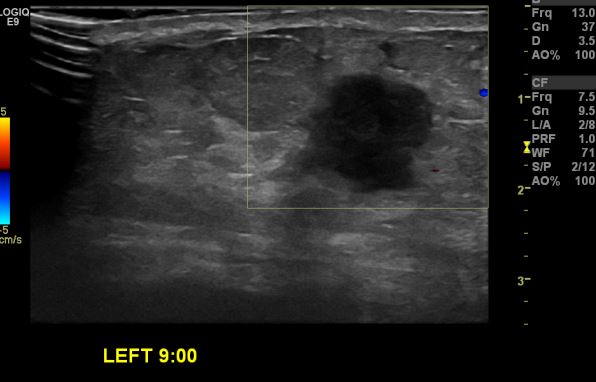

상기환자 좌측 유방에 멍울로 내원하신 60대 여성분으로 좌측유방 9시 방향에

만져지는 멍울 조직검사 시행하여 좌측 침윤성 유관암 진단 되었습니.